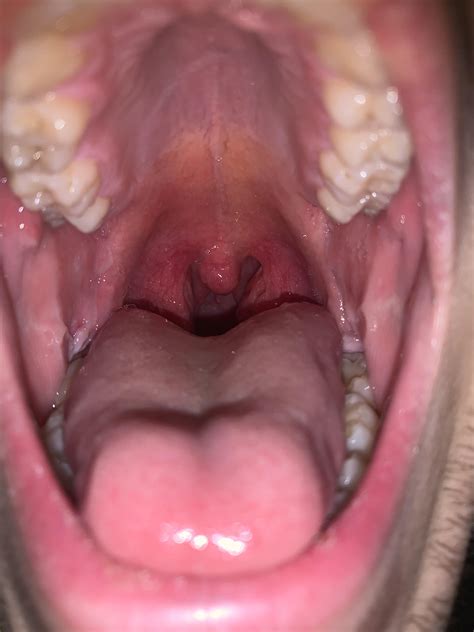

Many individuals become concerned when they observe their own throat anatomy in a mirror, often wondering if the shapes and sizes they see are typical or indicative of a medical issue. Understanding what normal tonsils images look like is the first step in differentiating between a healthy oral cavity and one that may require professional medical attention. Tonsils are part of the lymphatic system, designed to act as the body’s first line of defense against inhaled or ingested pathogens, which naturally causes them to vary in size and appearance from person to person.

Tonsils, specifically the palatine tonsils located on either side of the back of the throat, are clusters of lymphoid tissue. Because their job is to filter bacteria and viruses, they are constantly exposed to environmental factors. This is why it is common for people to search for normal tonsils images to see if their own tissue looks "too big" or "too bumpy."

In a healthy individual, tonsils often have the following characteristics:

• Color: They should match the pink or light red hue of the surrounding throat tissue.

• Texture: It is common for them to have small indentations known as crypts.

• Symmetry: While they don't have to be perfectly identical, they should be relatively similar in size.

• Absence of Symptoms: Healthy tonsils do not cause pain, difficulty swallowing, or chronic bad breath.

If you are looking at normal tonsils images, you will notice that the surface is rarely perfectly smooth. Those small craters or holes (crypts) are actually a healthy feature, though they can sometimes trap food debris.

Distinguishing between healthy tissue and a potential infection requires a keen eye. When people compare their throat to normal tonsils images, they are usually looking for red flags such as white patches, extreme swelling, or significant asymmetry. Below is a comparison table to help you identify the differences:

Feature Healthy Tonsils Infected/Abnormal Tonsils

Color Pink, matching the throat lining Bright red, inflamed, or dark red

Surface Pitted with small crypts Covered in white or yellow exudate/pus

Size Small to moderate, symmetric Severely enlarged (kissing tonsils)

Sensations None Pain, fever, or difficulty swallowing